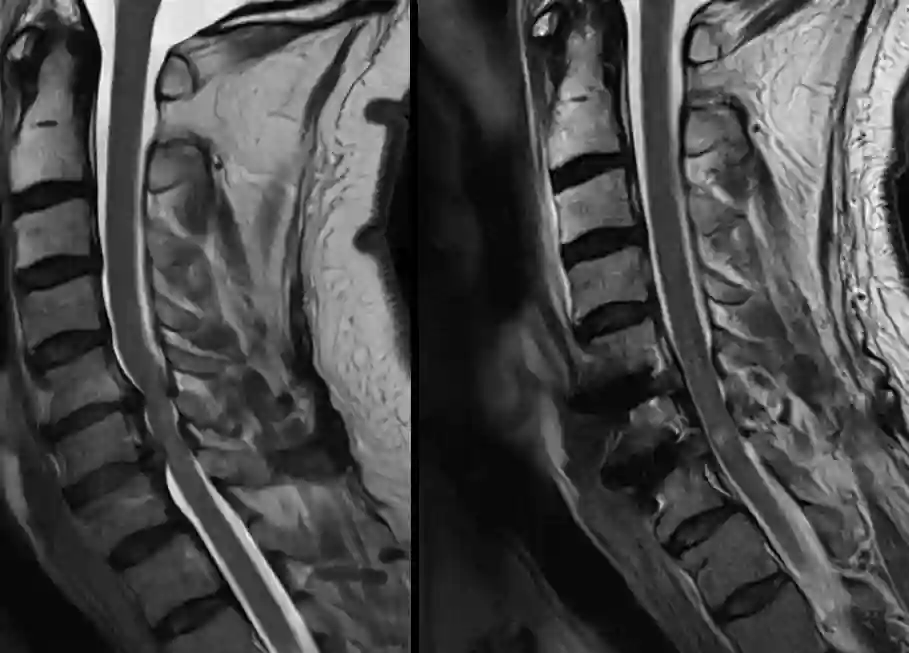

Linksseitig präoperatives MRT (T2 sagittale Sequenz) einer vorbestehenden Spinalkanalstenose nach einem Sturzereignis. Rechtsseitig postoperatives Bild nach zwei Höhen ACDF und Dekompression des Spinalkanals.